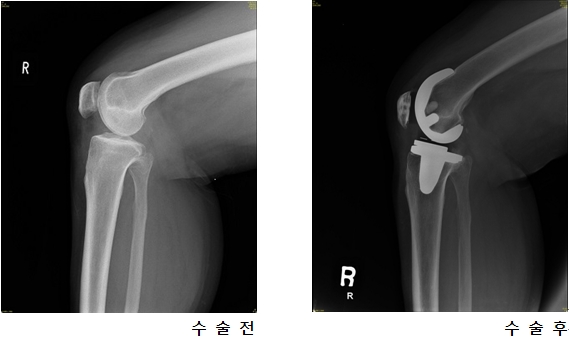

¡á Ãʱ⿡´Â ÁÖ»ç¿ä¹ý, ¹°¸®Ä¡·áµµ °¡´É, ½ÉÇÒ °æ¿ì Àΰø°üÀý ġȯ¼ú °í·Á

Ãʱ⿡ °üÀý¿°À» ¹ß°ßÇϰí Ä¡·á¸¦ ¹Þ°Ô µÇ¸é ¾à¹°Ä¡·á, ¹°¸®Ä¡·á, ¿îµ¿, ÁÖ»ç¿ä¹ýÀ» ÅëÇØ Ä¡·á°¡ °¡´ÉÇÏ´Ù. ÇÏÁö¸¸ °üÀý¿°Àº Ư¼º»ó Á¦ ¶§ Ä¡·á¸¦ ¹ÞÁö ¸øÇϸé Áõ»óÀÌ Á¡Á¡ ´õ ³ªºüÁö°Ô µÈ´Ù. ´õ ÀÌ»ó ºñ¼ö¼ú ¿ä¹ýÀ¸·Î Ä¡·á°¡ ºÒ°¡´ÉÇÒ ¶§´Â Àΰø°üÀý ġȯ¼úÀ» ¹Þ´Â °ÍÀÌ ÁÁ´Ù. Àΰø°üÀý ġȯ¼úÀ̶õ °üÀýÀÇ ¿¬°ñ ¼Ò½ÇÀÌ ½ÉÇÏ¿© º¯ÇüÀÌ µ¿¹ÝµÇ°í ±â´ÉÀÌ ¶³¾îÁ® ÅëÁõÀÌ ½ÉÇÒ ¶§ ¼Õ»óµÈ °üÀý¸éÀ» ±Ý¼Ó°ú ÇÃ¶ó½ºÆ½À¸·Î ÀÌ·ç¾îÁø »õ °üÀý·Î ´ëÄ¡ÇØ ÁÖ´Â ¼ö¼úÀ» ¸»ÇÑ´Ù. Àΰø°üÀý ¼ö¼úÀ̶ó´Â ¸»¿¡ ȯÀÚµéÀº °ÌºÎÅÍ ¸Ô°í ¼ö¼úÀ» ²¨¸®°Ô µÇ´Â °æ¿ì°¡ ¸¹Àºµ¥ ½ÇÁ¦·Î ¼ö¼ú °Ç¼öµµ ¸Å³â Áõ°¡Çϰí ÀÖÀ¸¸ç 95%ÀÇ ¼º°ø·ü°ú 15³â ÀÌ»óÀÇ ³»±¸¼ºÀ» °¡Áø ¾ÈÀüÇÑ ¼ö¼úÀÌ´Ù. ¼ö¼ú ÈÄ Á¤»óÀûÀ¸·Î ÀÏ»ó»ýȰ º¹±Íµµ ¹°·Ð °¡´ÉÇÏ´Ù. ÀÌ ¼ö¼úÀº °üÀý¿¡ µû¶ó ´Ù¸£Áö¸¸ °üÀýÀ» Àý°³ÇÏ°í ³°Àº °üÀýÀ» ¿ÏÀüÈ÷ Á¦°ÅÇÑ ÈÄ¿¡ »õ·Î ¸¸µç Àΰø°üÀýÀ» »ðÀÔÇÑ´Ù. Àΰø°üÀýÀº ÁÖ·Î Çձݰú Ư¼ö ÇÃ¶ó½ºÆ½À¸·Î ¸¸µé¾îÁ® ÀÖ´Ù.